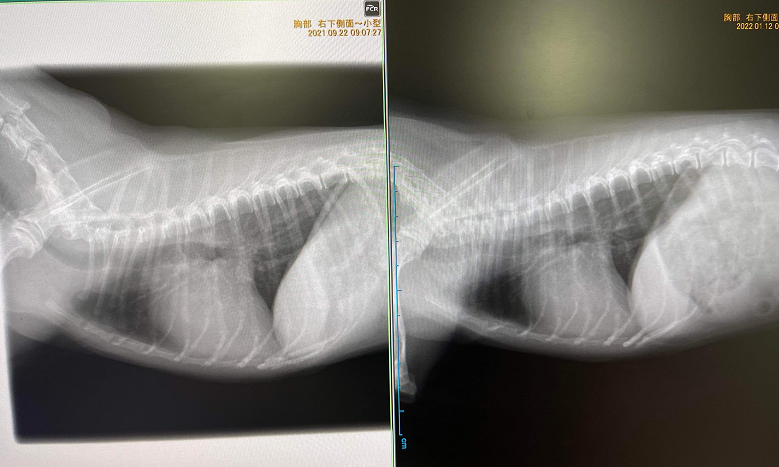

10月から「月のしずく」と「神秘の水 夢」を飲ませて、3ヶ月で心臓の肥大が少し小さくなり、肺の白い影が薄くなりました。

レントゲン写真撮ってきたので参考までに送ります。

微妙ですが変化してることがわかると思います。左が昨年9月、右が今年1月です。